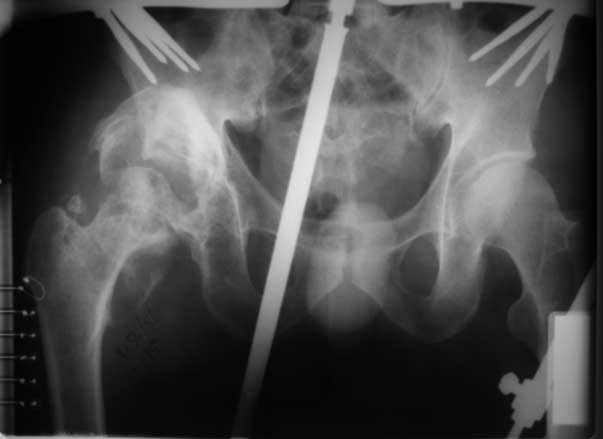

Имя     : поп.jpg

Url     : http://weborto.net:8080/pipermail/ortho/attachments/20090119/0ccb8dff/attachment-0005.jpg